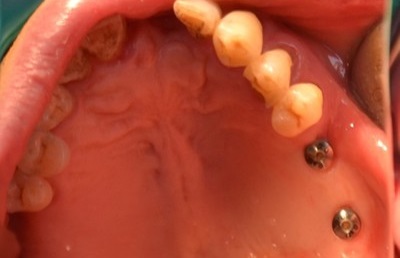

오차 없는 식립을 위한 ‘네비게이션 원리 임플란트’

기존 임플란트 방식인 절제가 아닌 무절제 (미세 절제)를 활용하여 출혈이나 부기의 우려가 적으며 염의 가능성이 크지 않아 빠른 일상 복원이 가능한 네비게이션 원리 임플란트는 관리 전 컴퓨터로 가상 관리를 시행하여 임플란트 위치를 결정해 미리 심어볼 수 있는 가이드 입니다.

임플란트의 안정성과 식립률을 높일 수 있는 방법이며 당뇨, 고혈압, 아픔에 대한 두려움을 가지고 있는 분들도 부담 없이 임플란트 심기가 가능합니다.

또한 네비게이션 원리 임플란트를 활용한 1DAY 임플란트를 통해 내원 당일 면담부터 임시 보철 식립까지 한 번에 받아보실 수 있으며 3회 내원으로 관리를 마칠 수 있습니다. (단, 잇몸 뼈가 건강한 분들에 한해 가능)